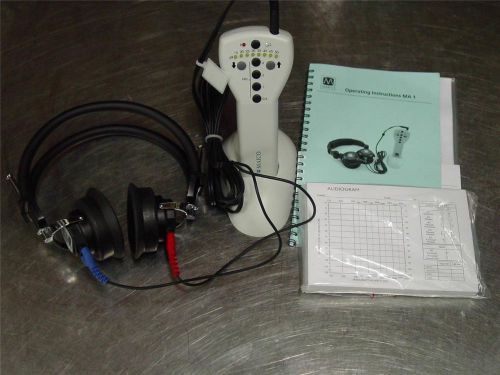

Maico MA1 handheld Audiometer with Headset